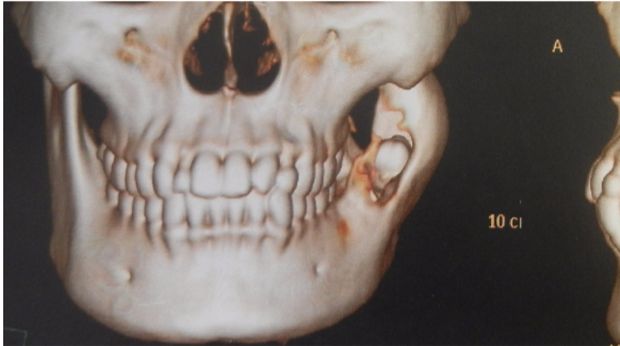

Tulang rahang yang menggelembung dan berisi cairan kistik (Foto: drg Dhanni Gustiana SpBMM) |

Tulang rahang yang menggelembung dan berisi cairan kistik (Foto: drg Dhanni Gustiana SpBMM)